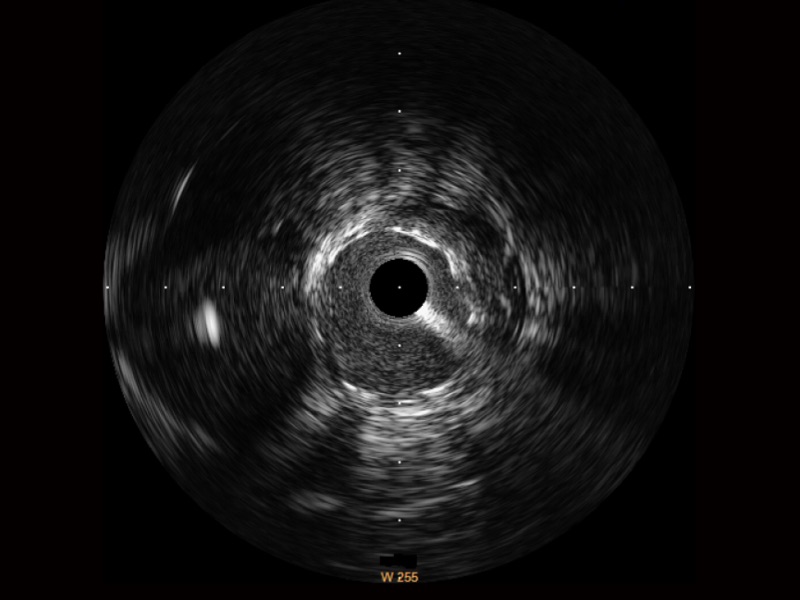

传统IVUS图像

对比传统IVUS导管成像,银河优越会宽频IVUS图像的近场支架梁显影更细腻,远场中膜外血管仍清晰可辨,兼顾远中近,兼顾分辨力与穿透深度